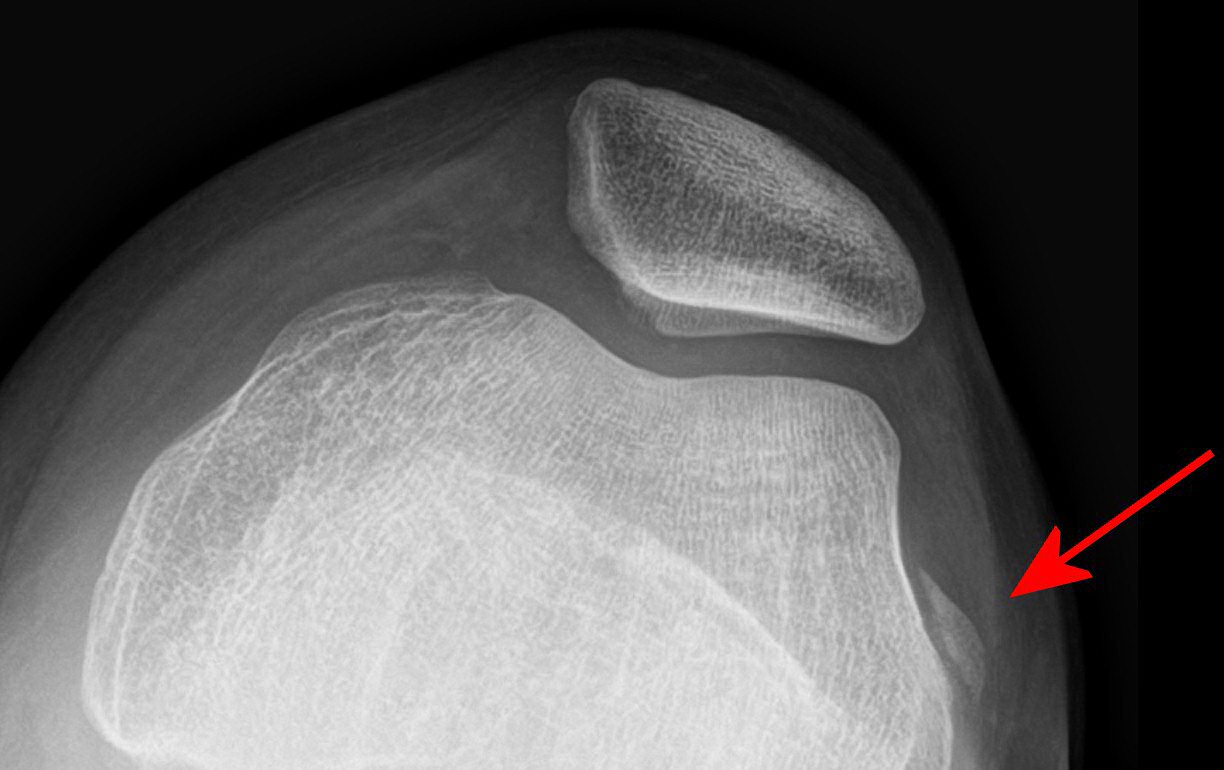

Slätröntgenbild där man kan se avlöst fragment som kommer från mediala patella. MR visade ca 2 cm osteokondralt fragment, opererades.